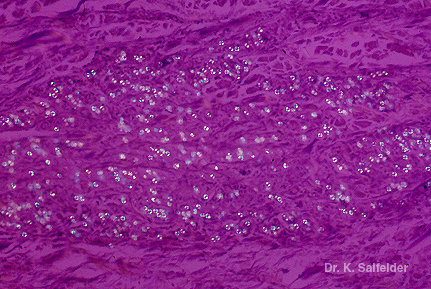

Abb. 14,16: Lobomykose

Schon bei schwacher Vergroesserung sind die zahlreichen hell aufleuchtenden Pilzzellen im polarisierten Licht zu sehen. HE-Faerbung